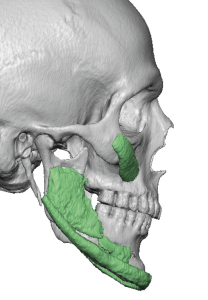

Custom designed or 3D jaw implants are the contemporary workhorse in lower facial asymmetry corrections. With modern patient-specific CT-based implant designing virtual planning an be done to design different right and left dimensions, matching the right and left sides of the jawline and centering the chain can be done far more accurately than stock implants ever could. 3D imaging is important because facial asymmetry is a true 3D problem and standard 2D assessment, even with plain x-rays and 2D CT scans, can not fully appreciate the extent of the asymmetries down to the millimeter level.

Determine the exact bony nature of the asymmetry.

- Smaller mandibular angle/body on one side

- Flat gonial angle

- Chin deviation/asymmetry

- ??Primary solution: Custom jawline implant

- Unilateral mandibular hypoplasia

- Jawline contour asymmetry

- Precise side-to-side correction

- Permanent structural change

- Can widen, lengthen, and reshape jaw

- Facial asymmetry is a multi-dimensional hard and softC tissue problem whose contemporary treatment requires 3D assessment and treatment planning.

- Most jaw asymmetries are best treated by a wrap around jawline implant approach to manage the bilateral deformities.